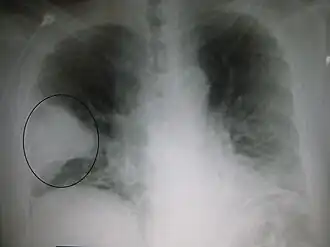

| Radiografia de tórax de pneumonia causada por gripe e Haemophilus influenzae. A seta indica consolidação. | |